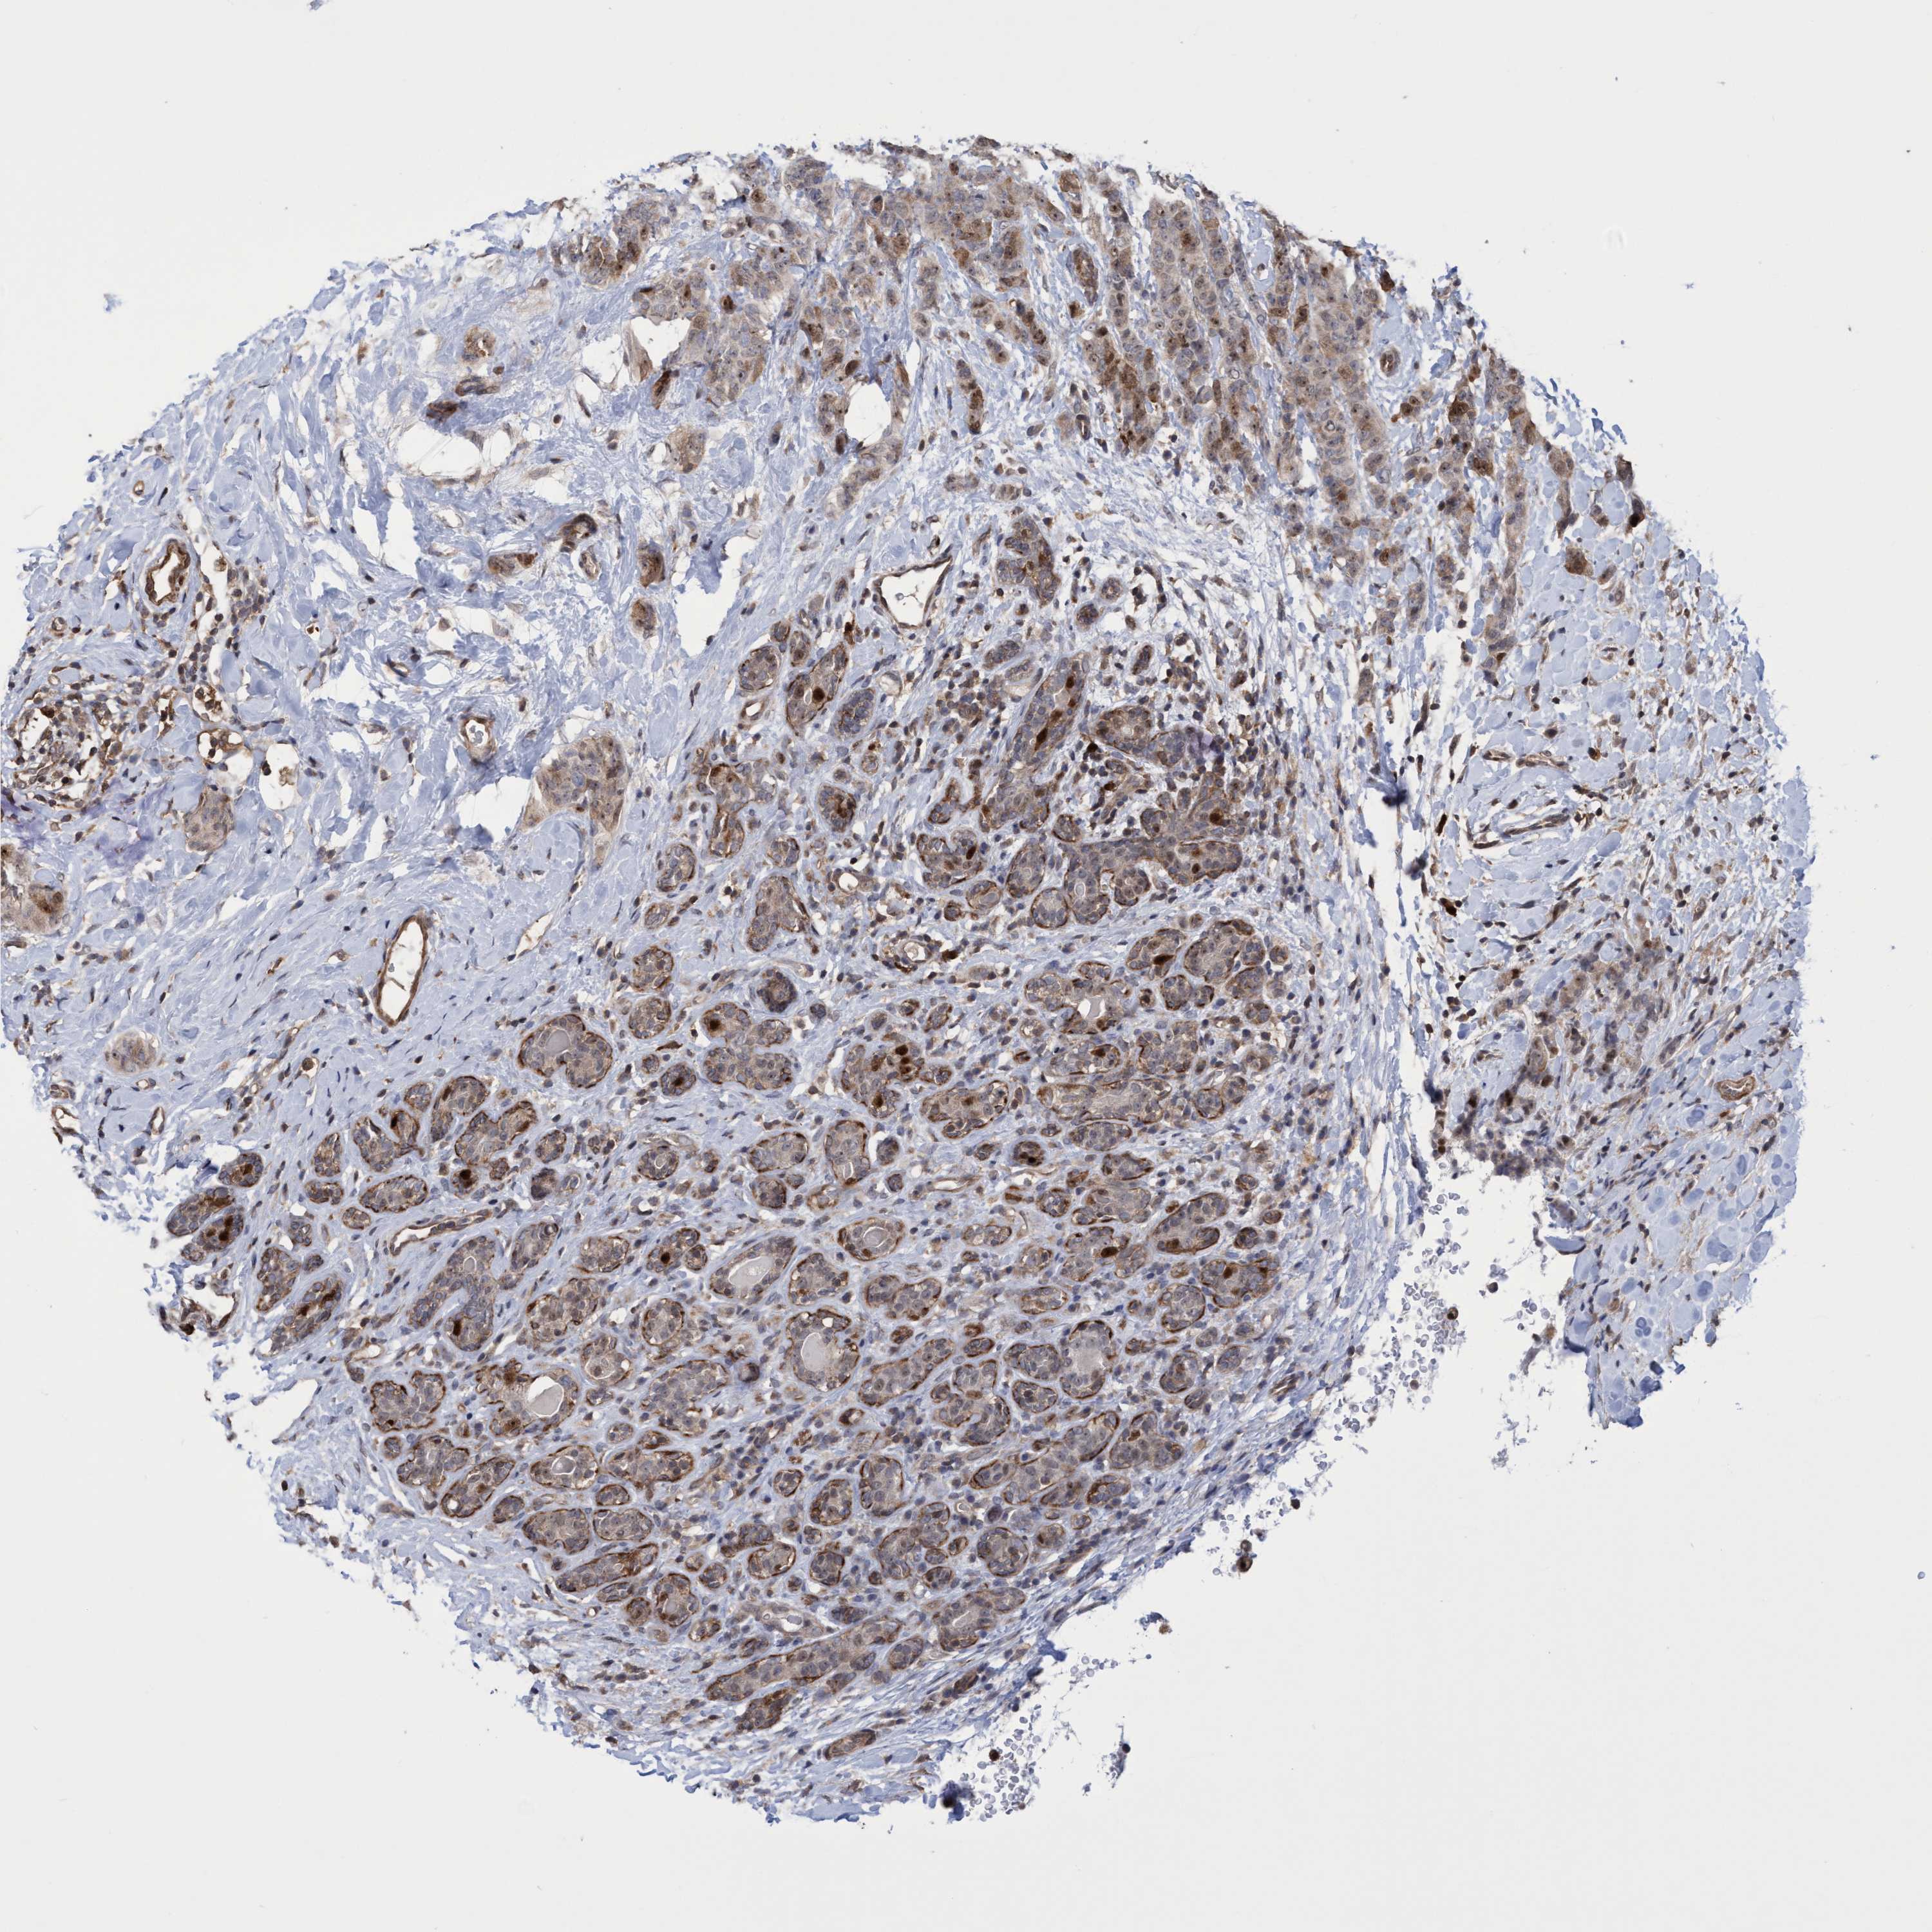

CANCER BREAST CANCER Show tissue menu

BRCA TCGA BRCA VALIDATION PROTEIN EXPRESSION